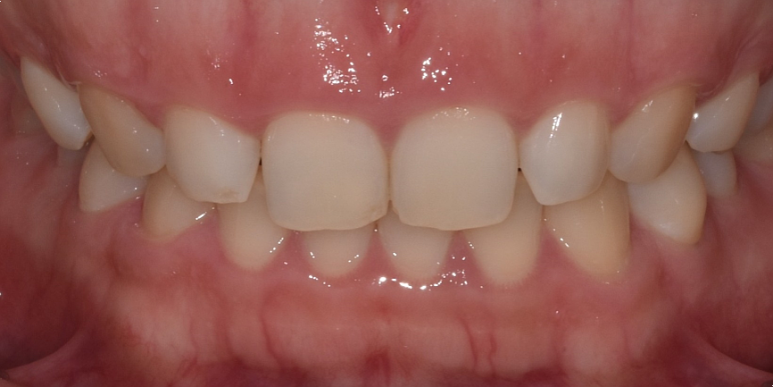

상기 환자분 전체적으로 잇몸라인이 평평하고, 치아가 네모나게 보이는 것이 고민이 되어 잇몸성형을 받기 위해 내원해 주셨습니다.

24세 여성

(전) 2022-06-11, (후) 2022-06-25

레이저를 이용해서 전체적으로 잇몸라인을 동그랗게 다듬어드리고 높이도 양측 균일하게 맞춰드렸습니다.

전후 사진 비교해 보시면 이전보다 치아 형태가 더 예쁘고 시원한 느낌이 드는 것을 확인하실 수 있는데요.

실제 웃거나 말씀하실 때 잇몸이 많이 보이는 것도 고민이셨는데, 이 부분도 개선되어 환자분도 많이 흡족해하셨습니다. ^^